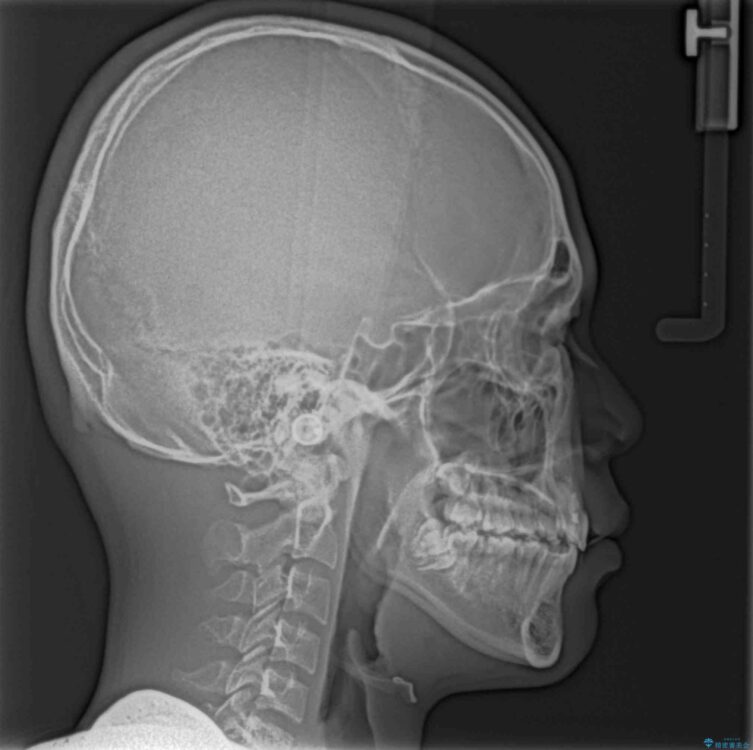

治療後

• 膨らんだ口元 ワイヤー装置での抜歯矯正 治療後画像